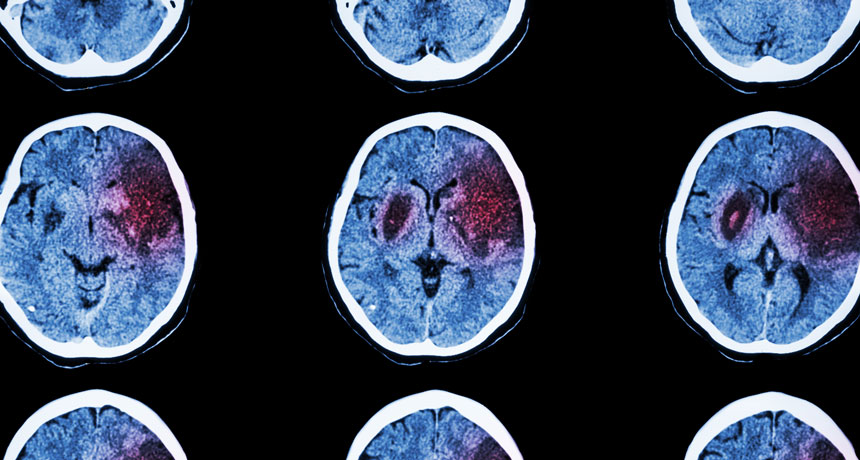

BRAIN ATTACK Most strokes in the United States are caused by a blood clot in the brain. Now scientists have linked a person’s immune response shortly after a stroke with a later loss in cognitive ability.

stockdevil/iStock